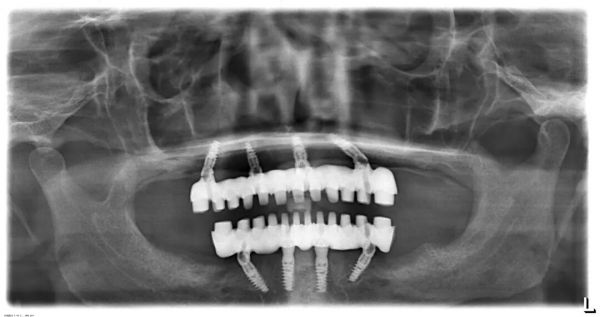

全口種植(如All-on-4/6技術(shù)):  通過在單頜植入4-6顆種植體作為“橋墩”,來支撐一整排固定的牙橋。這種方案往往具有以下巨大優(yōu)勢(shì):

強(qiáng)穩(wěn)定性:  說話、大笑、咳嗽時(shí)紋絲不動(dòng),告別假牙脫落的尷尬。

強(qiáng)大咀嚼力:  能恢復(fù)接近真牙的咀嚼功能,可以正常飲食。

保護(hù)骨骼:  防止牙槽骨萎縮,維持面部年輕態(tài)。

舒適度高:  沒有大基托,無異物感,不影響味覺。